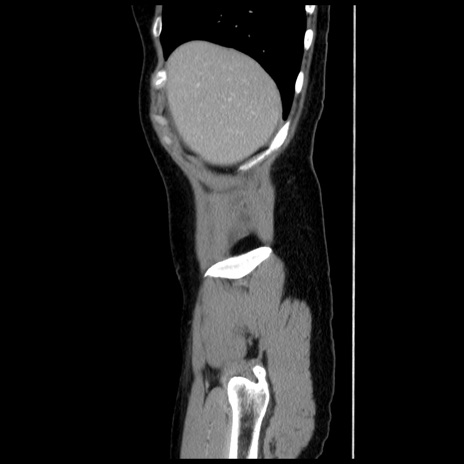

症例10(矢状断像)

【症例】 50歳代女性

【主訴】 腹痛

【現病歴】前日生レバーを食べた。今朝に排便あり。 昼前に突然発症の腹痛を生じ、当院救急外来を受診した。

【既往歴】 子宮筋腫にてで子宮全摘後

【身体所見】 意識清明、腹部:平坦、軟、下腹部やや左を中心に圧痛・反跳痛あり、筋性防御あり

【データ】WBC 7800、CRP 0.07